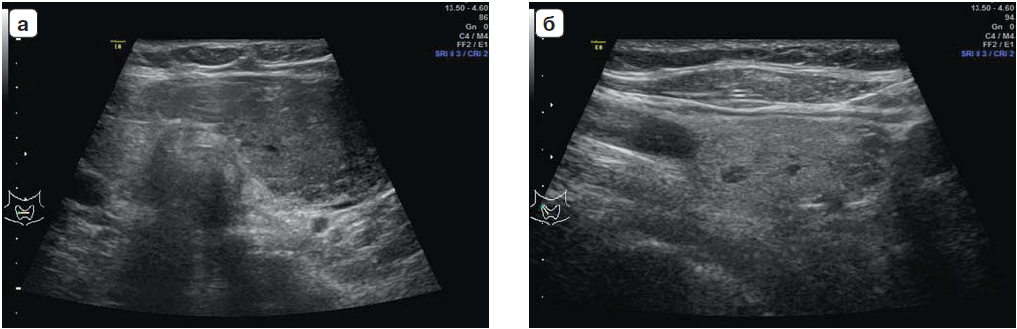

Через год было проведено ультразвуковое исследование в динамике в ФГБУ ЭНЦ МЗ РФ, по результатам которого общий объем ЩЖ составил 60,5 мл, объем левой доли – 55 мл, в ней же гипоэхогенное с четкими контурами образование неоднородной структуры, размерами 3,0 × 6,0 × × 7,2 см, сходной топографии с ранее приведенными ультразвуковыми данными. Также в просвете в верхней трети внутренней яремной вены выявлено образование средней эхогенности с четкими контурами размером 2,3 × 1,4 см (рис. 1).

Рис. 1. Ультразвуковое исследование органов шеи пациентки: а – в левой доле щитовидной железы определяется объемное конгломератное образование; б – в просвете прилежащей внутренней яремной вены образование неоднородной структуры.

1. Рис. 1. Ультразвуковое исследование органов шеи пациентки: а – в левой доле щитовидной железы определяется объемное конгломератное образование; б – в просвете прилежащей внутренней яремной вены образование неоднородной структуры.